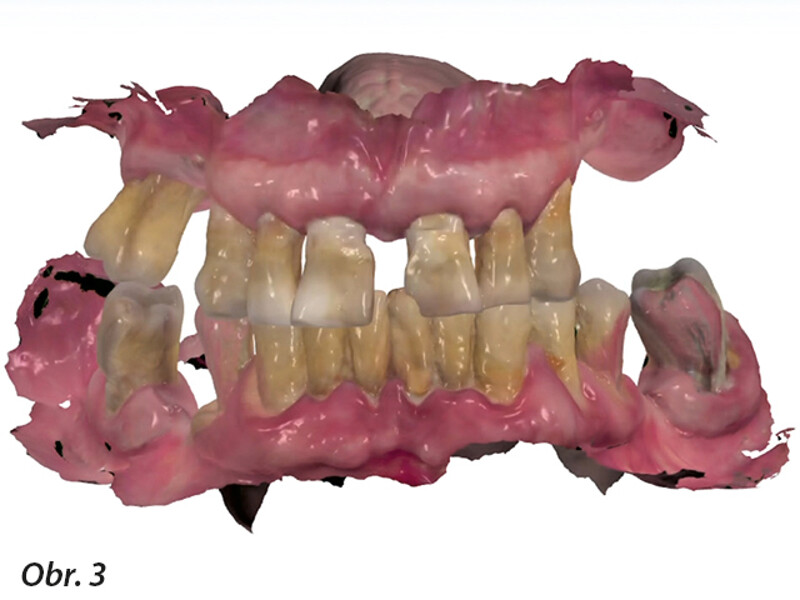

Plně digitální Pro Arch protokol